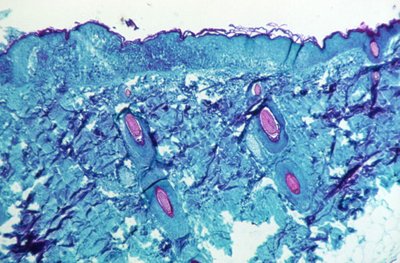

A section of skin tissue, harvested from a lesion on the skin of a monkey, that had been infected with monkeypox virus

A section of skin tissue, harvested from a lesion on the skin of a monkey, that had been infected with monkeypox virus, is seen at 50X magnification on day four of rash development in 1968. CDC/Handout via REUTERS. THIS IMAGE HAS BEEN SUPPLIED BY A THIRD PARTY. IT IS DISTRIBUTED, EXACTLY AS RECEIVED BY REUTERS, AS A SERVICE TO CLIENTS